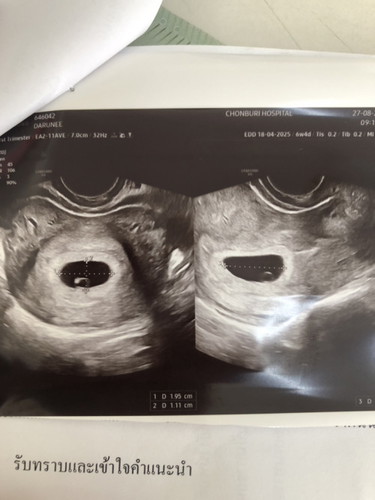

อัลตราซาวด์ทางช่องคลอด

ตอนไปซาวด์น้องครั้งแรกหมอบอกน้องตัวจิ๋วมากตอนนี้ได้8wวันที่17นี้หมอนัดแม่แอบกังวลว่าลูกจะตัวจิ๋วเหมือนเดิมจังเลยค่ะ